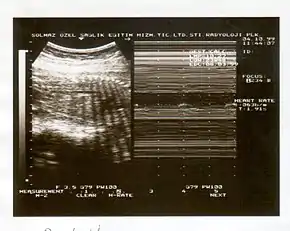

A biophysical profile (BPP) is a prenatal ultrasound evaluation of fetal well-being involving a scoring system,[1] with the score being termed Manning's score.[2] It is often done when a non-stress test (NST) is non reactive, or for other obstetrical indications.

The BPP has 5 components: 4 ultrasound (US) assessments and an NST. The NST evaluates fetal heart rate and response to fetal movement. The five discrete biophysical variables:

- Fetal heart rate

- Fetal breathing

- Fetal movement

- Fetal tone

- Amniotic fluid volume